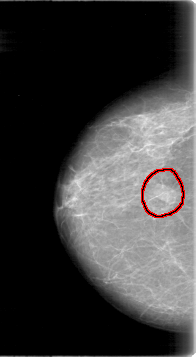

FILE: D_4015_1.RIGHT_MLO.OVERLAY

TOTAL_ABNORMALITIES 1

ABNORMALITY 1

LESION_TYPE MASS SHAPE OVAL MARGINS OBSCURED

ASSESSMENT 0

SUBTLETY 4

PATHOLOGY BENIGN

TOTAL_OUTLINES 1

BOUNDARY